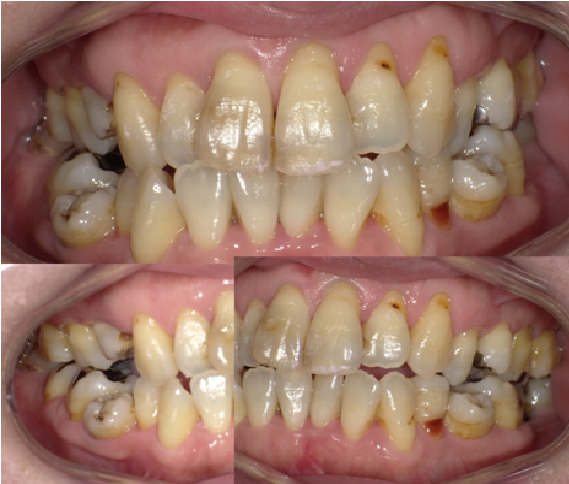

④被せ物や詰め物が劣化して変色している

保険のプラスチックの被せ物や詰め物は2、3年ほど経つと黄色く変色してきてしまいます。そして土台に金属を使っている場合、根元や歯茎が黒くなり汚く見えることがあります。痛みや腫れもなく機能的には問題はないのもかかわらず、歯をきれいにするには変色や劣化する金属を必要としないオールセラミックで治療をお勧めします。

⑤虫歯で汚く見える

前歯が虫歯になると、黒や茶色や黄色やグレーに染まって歯が汚く見えます。前歯は歯と歯の間の虫歯になりやすく、気づかずに進行し、急に穴が開いて初めて気づくことが多いです。小さい虫歯であれば歯と同じ色のプラスチックを詰めることで1日で治せるため、虫歯が広がる前に歯の変色に気づいて歯医者で治療をしてください。

⑦銀歯が多く口の中にあり汚く見える

口に中に銀歯があると汚く見えます。歯の色は本来の色は白に近いです。銀歯がたくさんあると口の中が黒っぽくなり、汚く見えます。前述しましたように、小さい銀歯ならプラスチックで、大きなものはセラミックで治療すると、白くできるので口の中全体がきれいに美しく見えます。